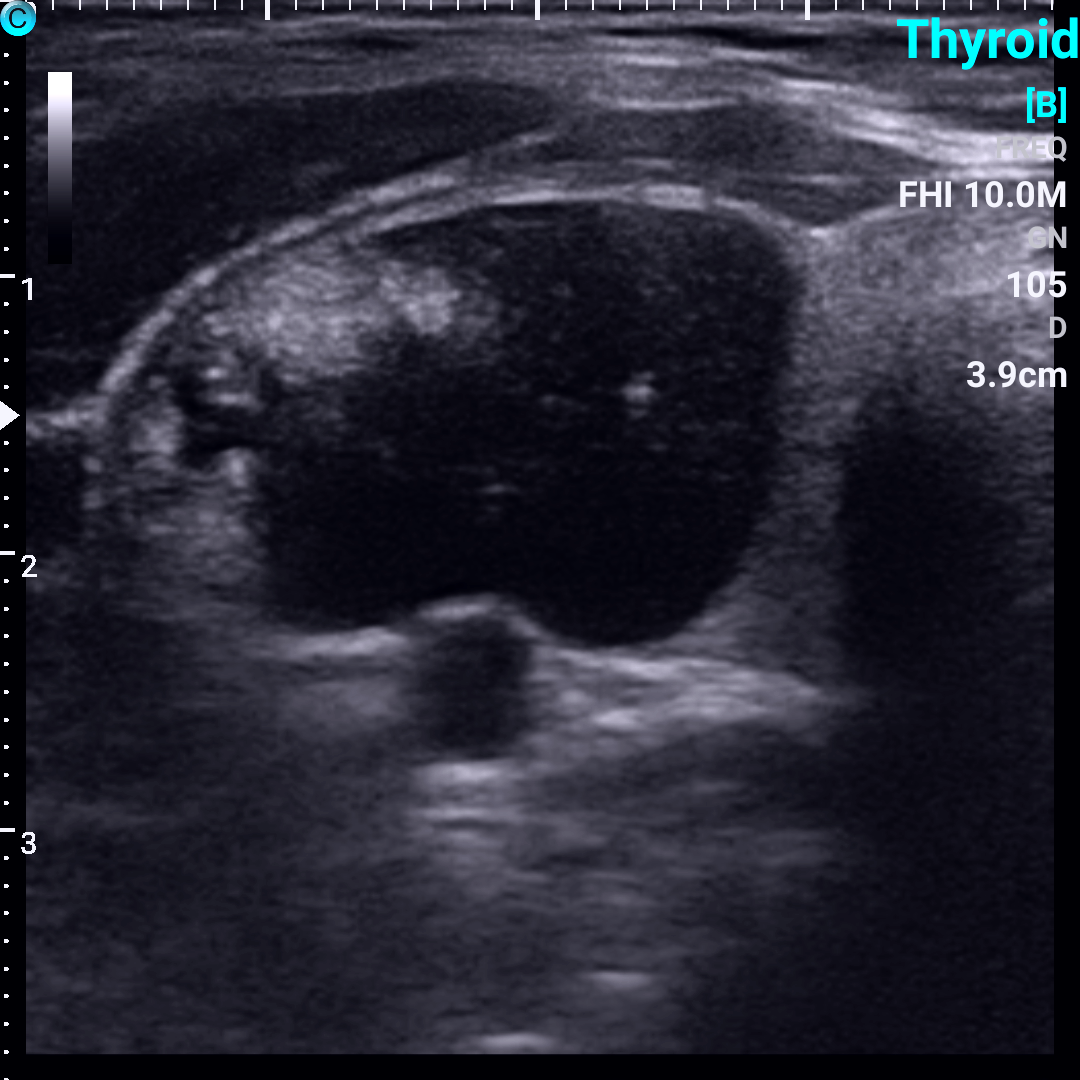

甲状腺结节超声图像解读?

对于已经发现甲状腺结节或怀疑甲状腺结节的患者,超声检查是首选的检查方法。

04、看囊实性

依据结节内部成分的不同可以将结节分为:

1. 囊性结节:内部成分为液体;

2. 实性结节:内部成分为固体;

3. 囊实性结节:内部成分既有液体,也有固体。

恶变的几率依次为:实性结节>囊实性结节>单个的囊性结节>多发的囊性结节。

甲状腺囊性,囊实性和实性结节超声图像